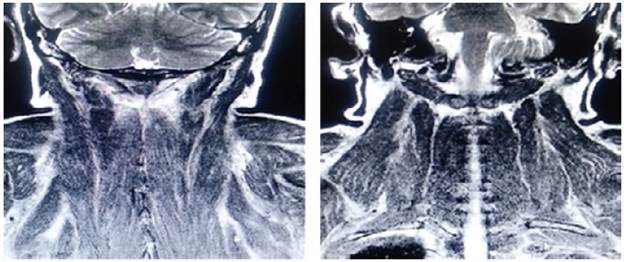

On admission, myopathy studies were initiated (Table 1) and muscle enzymes, electromyography and muscle biopsy were requested, which excluded inflammatory myopathy. The autoimmune profile and HIV were negative. Adult Pompe disease was considered, but acid maltase was normal and syringomyelia was ruled out using contrast-enhanced cervical and brain MRI (Figure 3). Considering the lytic lesions observed in chest tomography, neoplasms (myopathy as a paraneoplastic phenomenon) were looked for as there was no compromise of the pulmonary parenchyma, only bibasal subsegmental atelectasis. No masses or organomegaly were observed in abdomen images (Figure 4).